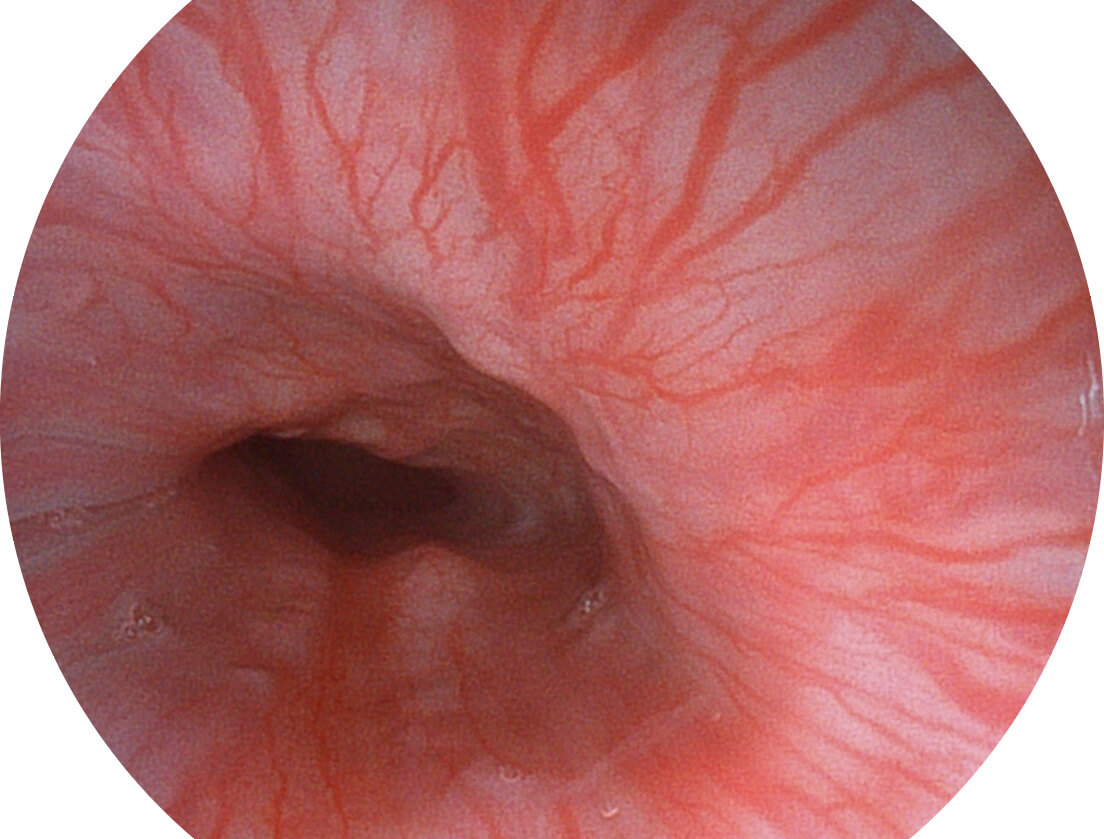

图像具有高亮度、高黏膜血管颜色对比度的特点,且不改变粘液、食物残渣、粪便的基本颜色,可在中远景下进行观察,助力消化道早期疾病的诊断。

SFI图像

白光图像